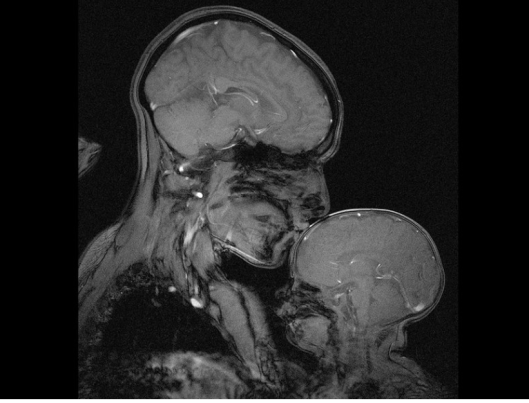

In the age of MRIs, a new form of art is emerging. Capturing the brains of people at their most intimate moments, like this mother and child:

(credit: Rebecca Saxe and Atsushi Takahashi / Department of Brain and Cognitive Sciences, MIT / Athinoula A. Martinos Imaging Center at the McGovern Institute for Brain Research, MIT)